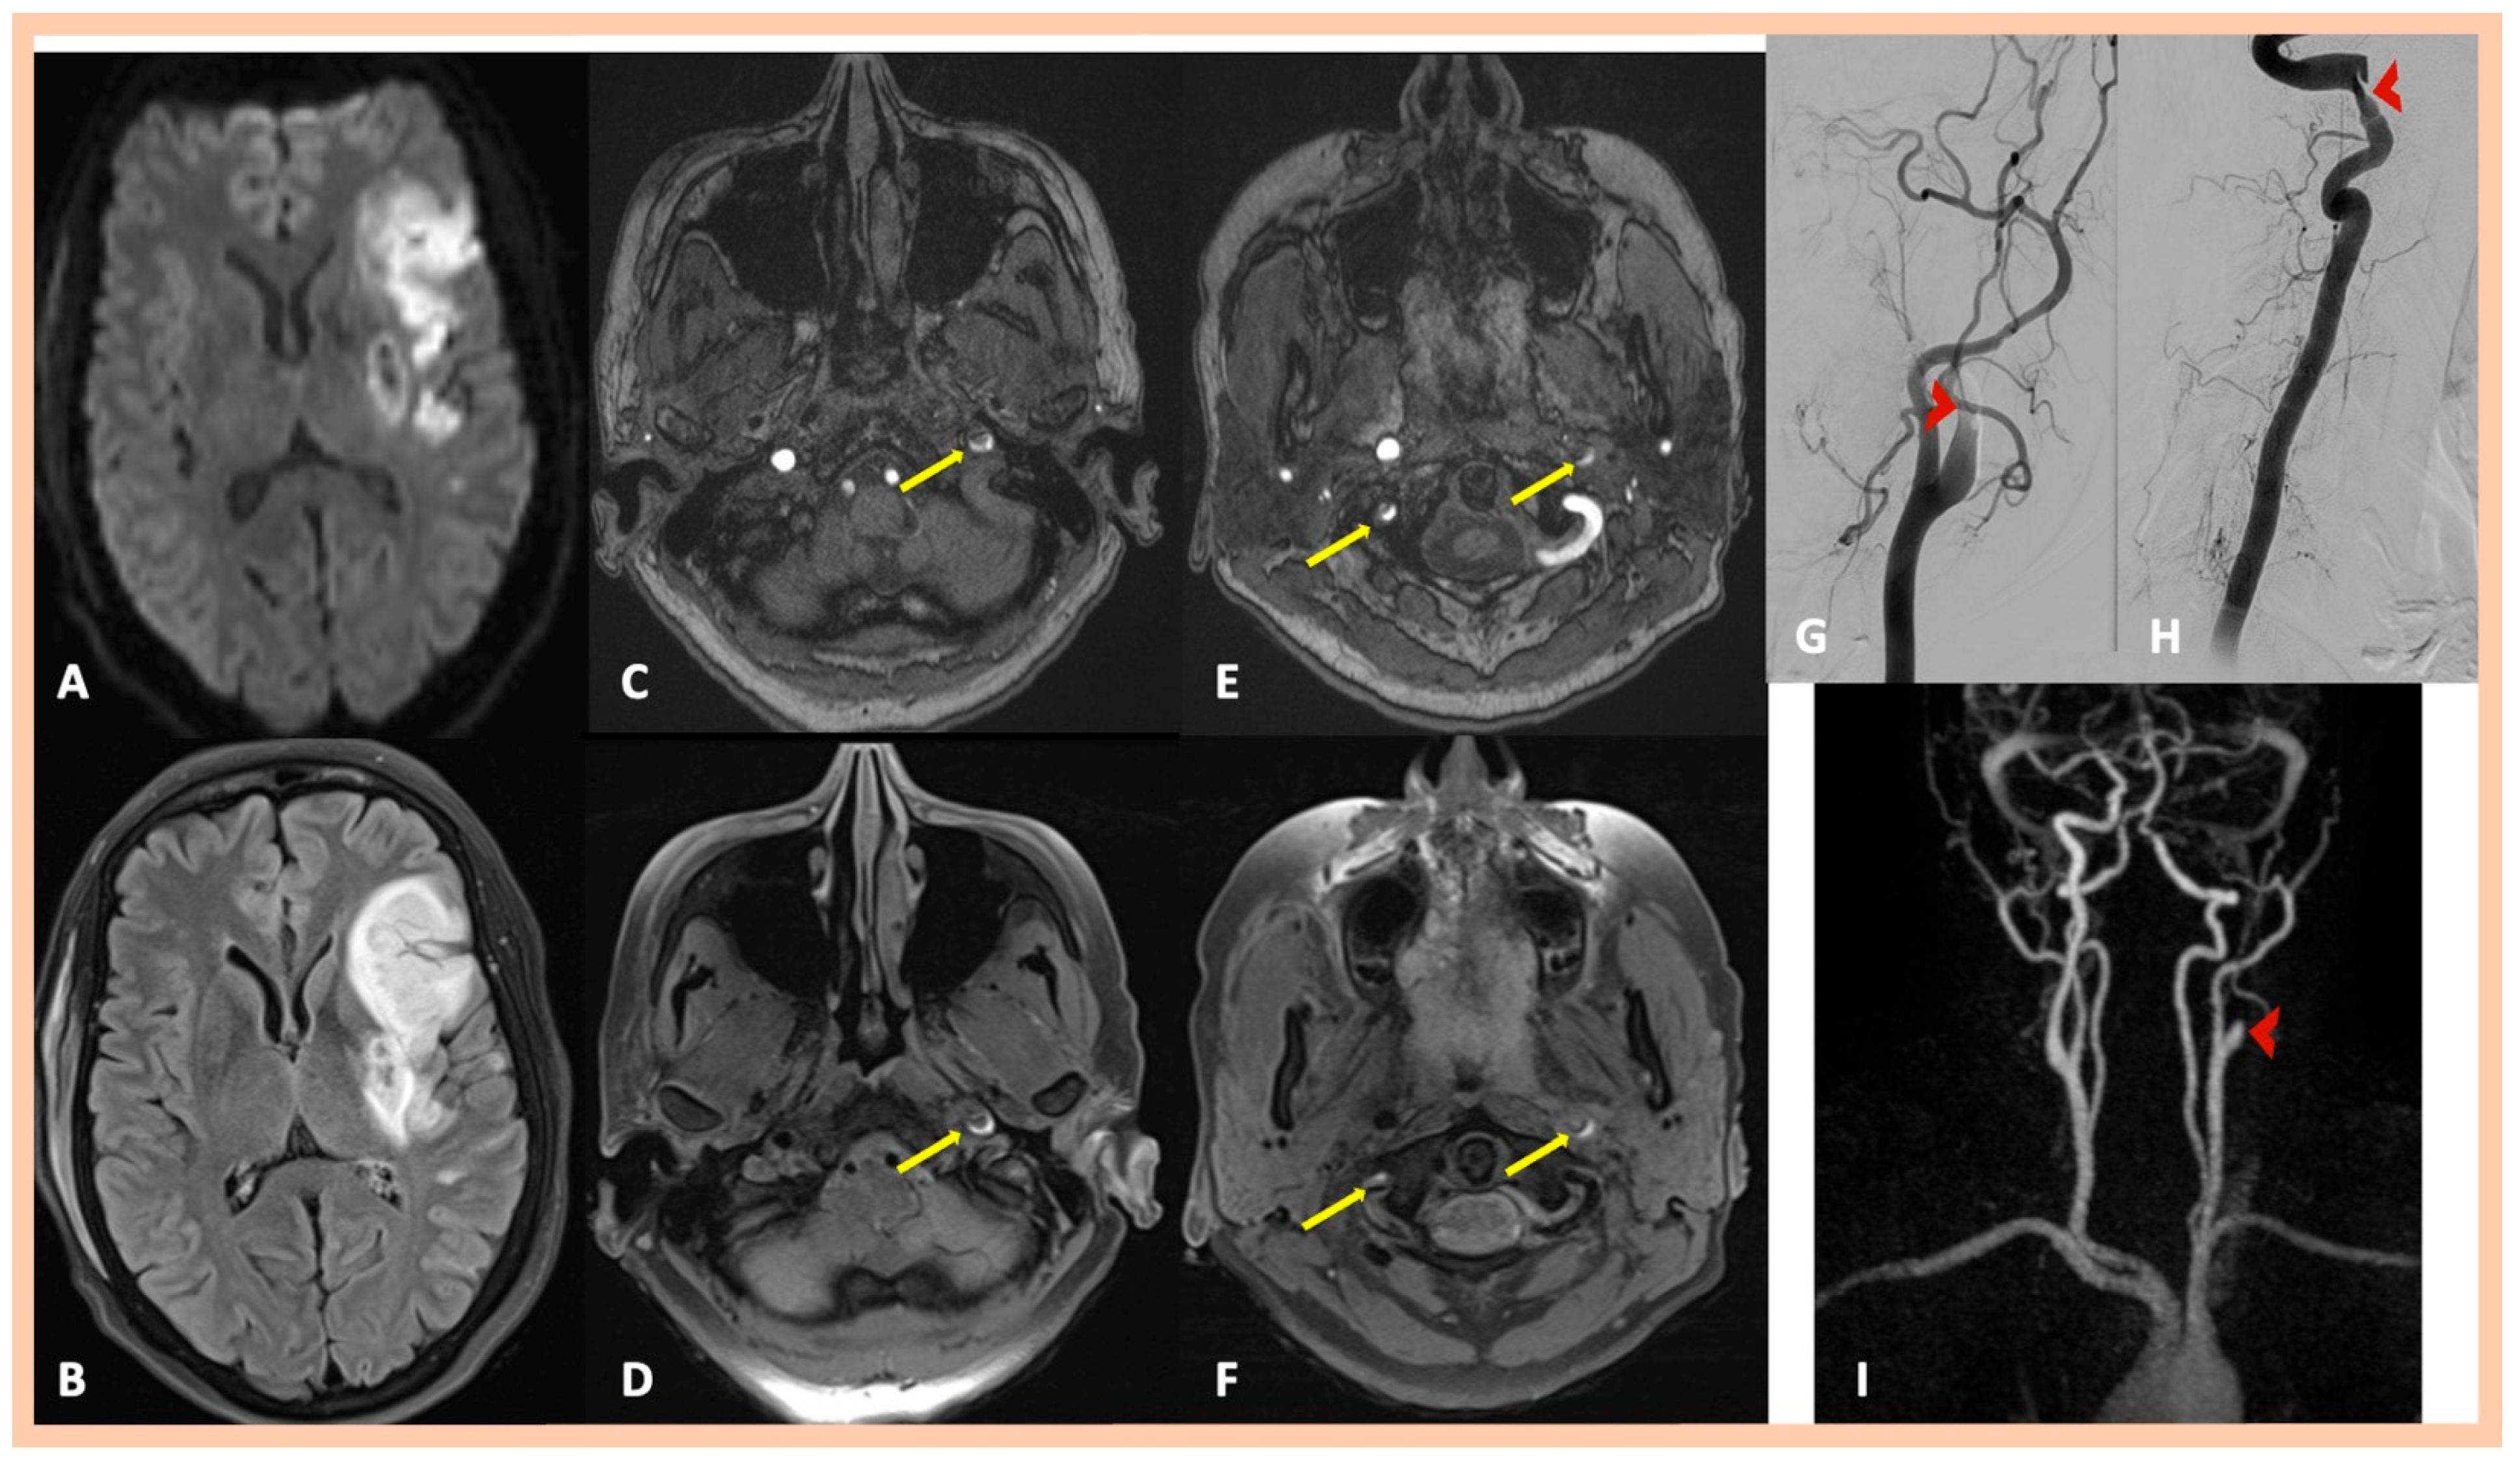

| Pat. #1 | Acute right MCA infarction | Right internal carotid “flame-like” occlusion (≈1 cm above the bifurcation) | Intramural hematoma along the distal cervical and proximal petrous artery segments and mural hematoma in the intraforaminal segment of the right (V2) vertebral artery | Confirmed MRA findings | Symptomatic right ICA and asymptomatic right V2 dissections | 2 | No |

| Pat. #2 | Acute left MCA infarction | Left internal carotid “flame-like” occlusion (≈1 cm above the bifurcation) | Intramural hematoma along the distal cervical and proximal petrous artery segments of the left ICA. and Mural hematoma in the intraforaminal segment of the right (V2) vertebral artery | Confirmed MRA findings | Symptomatic left ICA dissection and asymptomatic right V2 dissection | 2 | No |